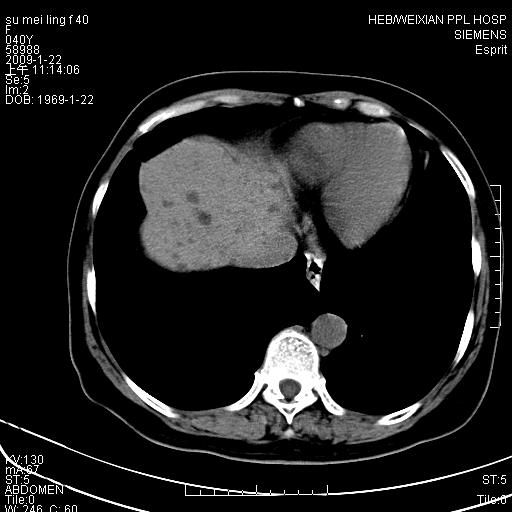

主因食欲不振检查。b超检查肝内片状低密度影。

图象的序列乱,病史也简单,单看这几幅图片考虑——肝囊肿?转移瘤?建议强化

以肝多发性囊肿可能大

我个人认为转移瘤可能性大!建议增强!

考虑多发肝小囊肿,建议增强,不排除囊性转移可能。

多发肝囊肿或caroli

肝内多发囊性低密度灶,以肝囊肿可能性大;建议必要时行进一步检查。

囊性病变沿胆管走向,首先考虑肝内胆管囊肿(caroli)、多发肝囊肿不除外